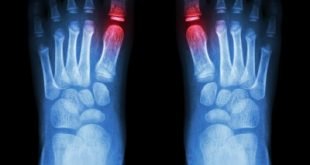

Tag Archives: rheumatoid arthritis

farmasetika.com – Telah banyak penelitian yang dilakukan mengenai pengobatan radang sendi, salah satu perkembangan terbarunya yaitu obat Kevzara (Sarilumab). Obat ini dapat mengatasi radang sendi yang terjadi pada penderita dewasa. Obat Kevzara mengandung bahan aktif sarilumab. Peradangan sendi atau Rheumatoid arthritis merupakan penyakit yang disebabkan terganggunya sistem kekebalan tubuh yang …

rheumatoid arthritis